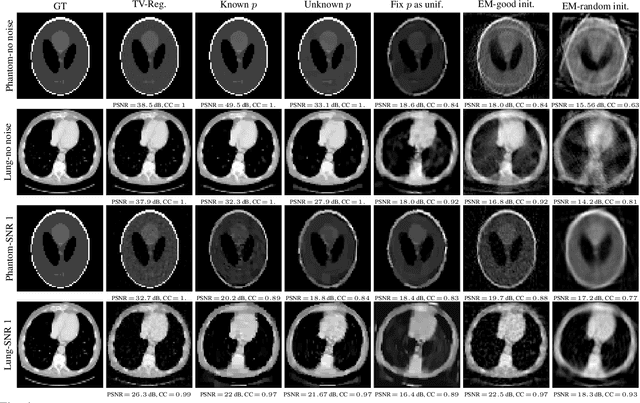

Abstract:Unknown-view tomography (UVT) reconstructs a 3D density map from its 2D projections at unknown, random orientations. A line of work starting with Kam (1980) employs the method of moments (MoM) with rotation-invariant Fourier features to solve UVT in the frequency domain, assuming that the orientations are uniformly distributed. This line of work includes the recent orthogonal matrix retrieval (OMR) approaches based on matrix factorization, which, while elegant, either require side information about the density that is not available, or fail to be sufficiently robust. In order for OMR to break free from those restrictions, we propose to jointly recover the density map and the orthogonal matrices by requiring that they be mutually consistent. We regularize the resulting non-convex optimization problem by a denoised reference projection and a nonnegativity constraint. This is enabled by the new closed-form expressions for spatial autocorrelation features. Further, we design an easy-to-compute initial density map which effectively mitigates the non-convexity of the reconstruction problem. Experimental results show that the proposed OMR with spatial consensus is more robust and performs significantly better than the previous state-of-the-art OMR approach in the typical low-SNR scenario of 3D UVT.